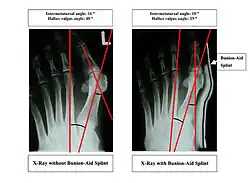

Orthotics

Orthotics are splints or regulators while conservative measures include various footwear like toe spacers, valgus splints, and bunion shields. Toe spacers seem to be effective in reducing pain, but there is no evidence that any of these techniques reduces the physical deformity. There are a variety of available orthotics including off-the-shelf commercial products and custom-molded orthotics, which may be prescribed medical devices.[14]